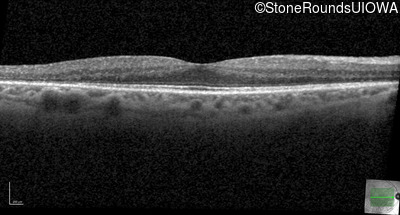

Optical Coherence Tomography - Right - 20/20

Exemplar / OCT Stack

OCT Stack